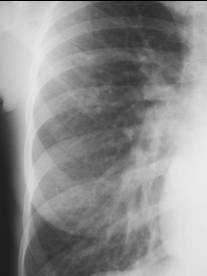

Increased Flow

PAH